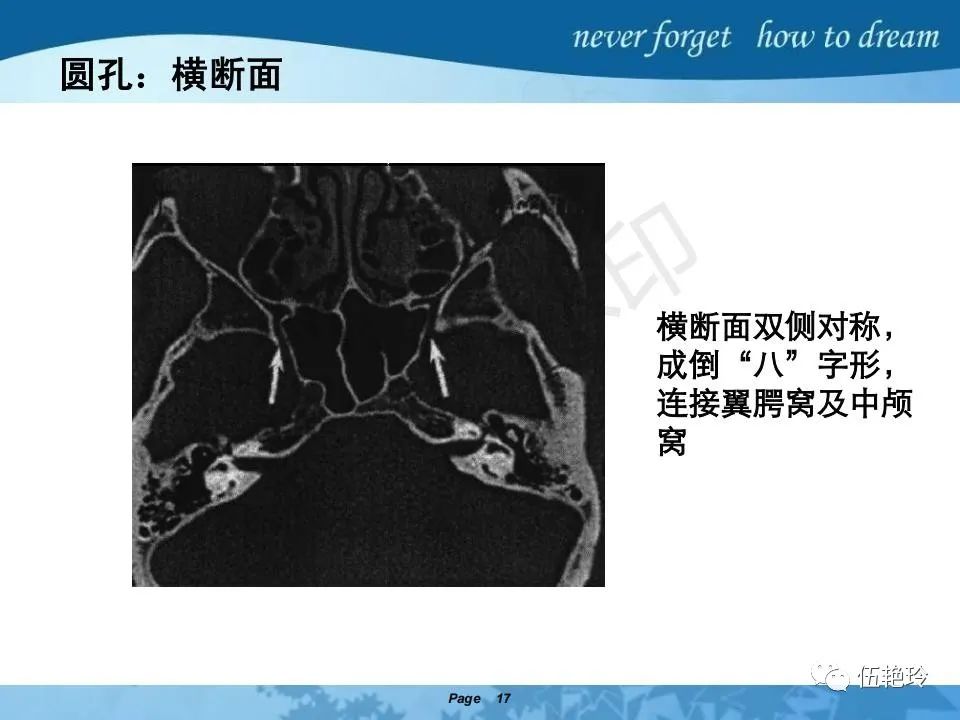

翼腭窝的解剖结构与鼻咽癌侵犯

2.31 向上颅内:①鼻咽顶壁→破裂孔(岩尖、斜坡)→蝶窦、海绵窦;②鼻咽顶壁→蝶骨基底部→蝶窦、海绵窦;③鼻咽侧壁→茎突前间隙→蝶骨大翼(卵圆孔)→海绵窦;④鼻咽侧壁→茎突前间隙→翼腭窝→ 颞下窝;⑤鼻咽前壁→鼻腔→翼突、翼腭窝→眶下裂→眶尖→海绵窦;⑥鼻咽前壁→鼻腔→上颌窦、筛窦;